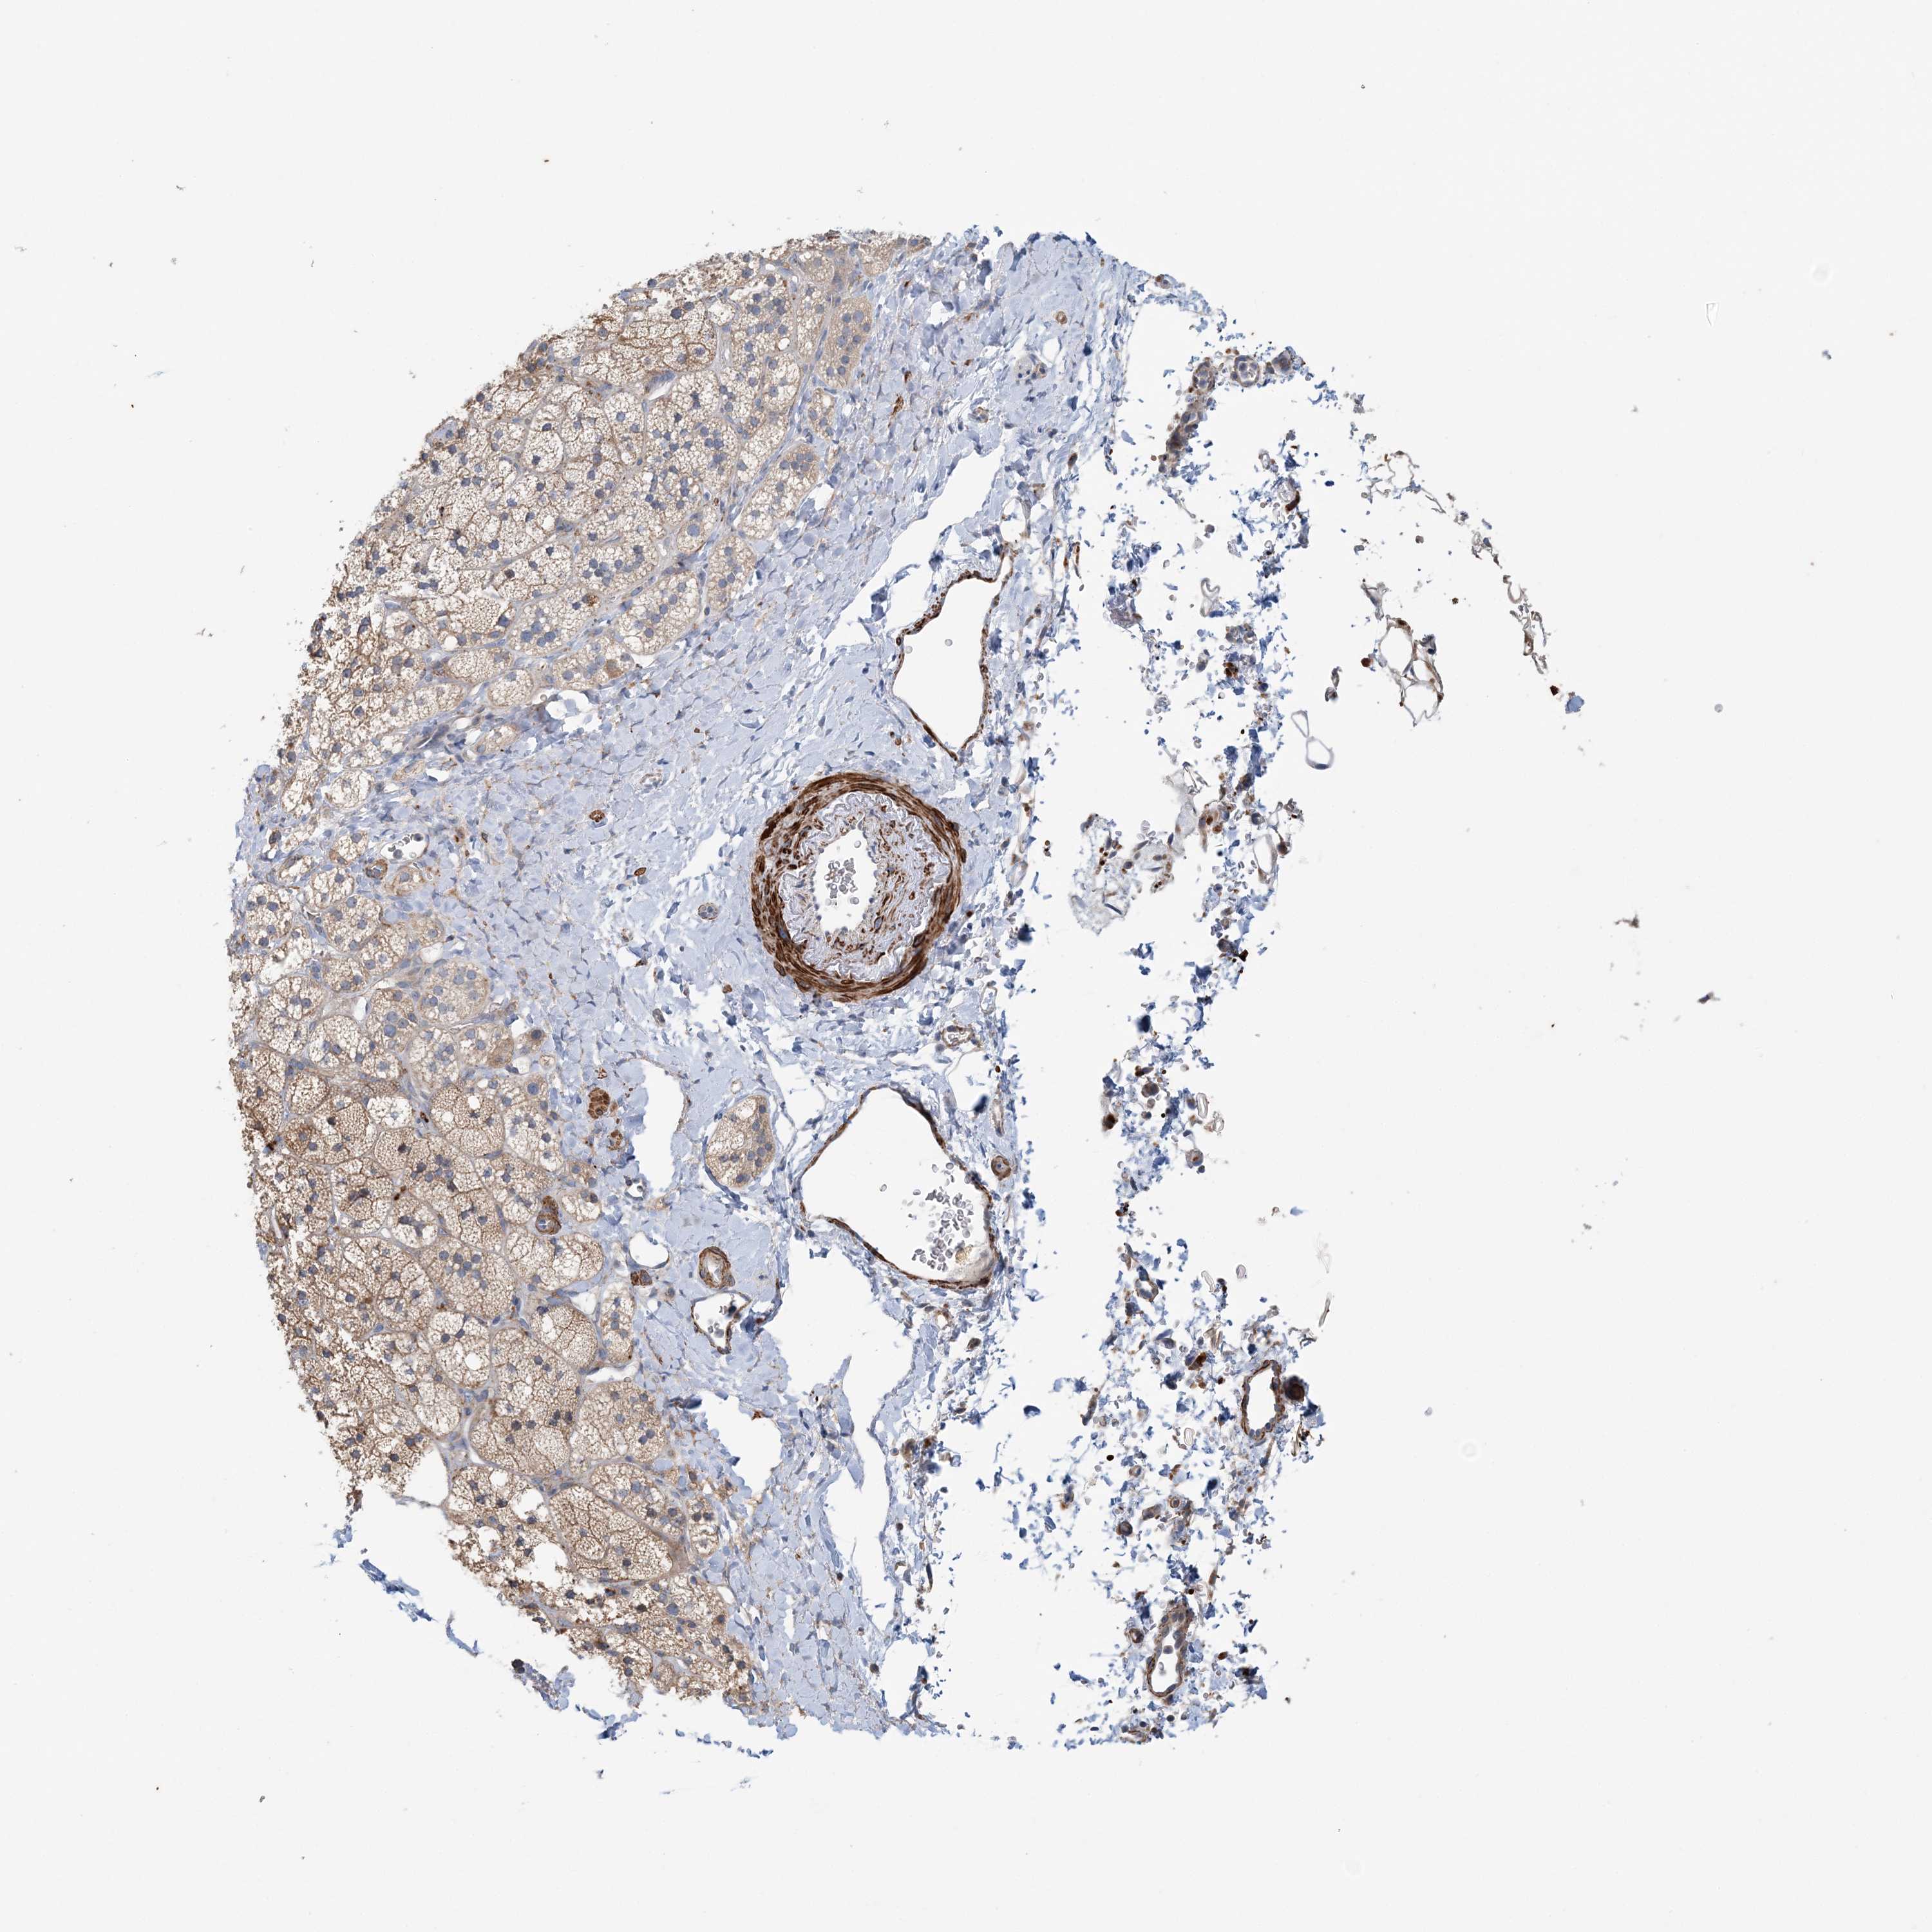

ADRENAL GLAND - Antibody stainingi

Antibody staining in the annotated cell types in the current human tissue is reported as not detected, low, medium, or high, based on conventional immunohistochemistry profiling in selected tissues. This score is based on the combination of the staining intensity and fraction of stained cells.

Each image is clickable and will lead to virtual microscopy that enables deeper exploration of all samples and also displays staining intensity scores, fraction scores and subcellular localization as well as patient and tissue information for each sample.

Antibody CAB034230

Glandular cells Medium